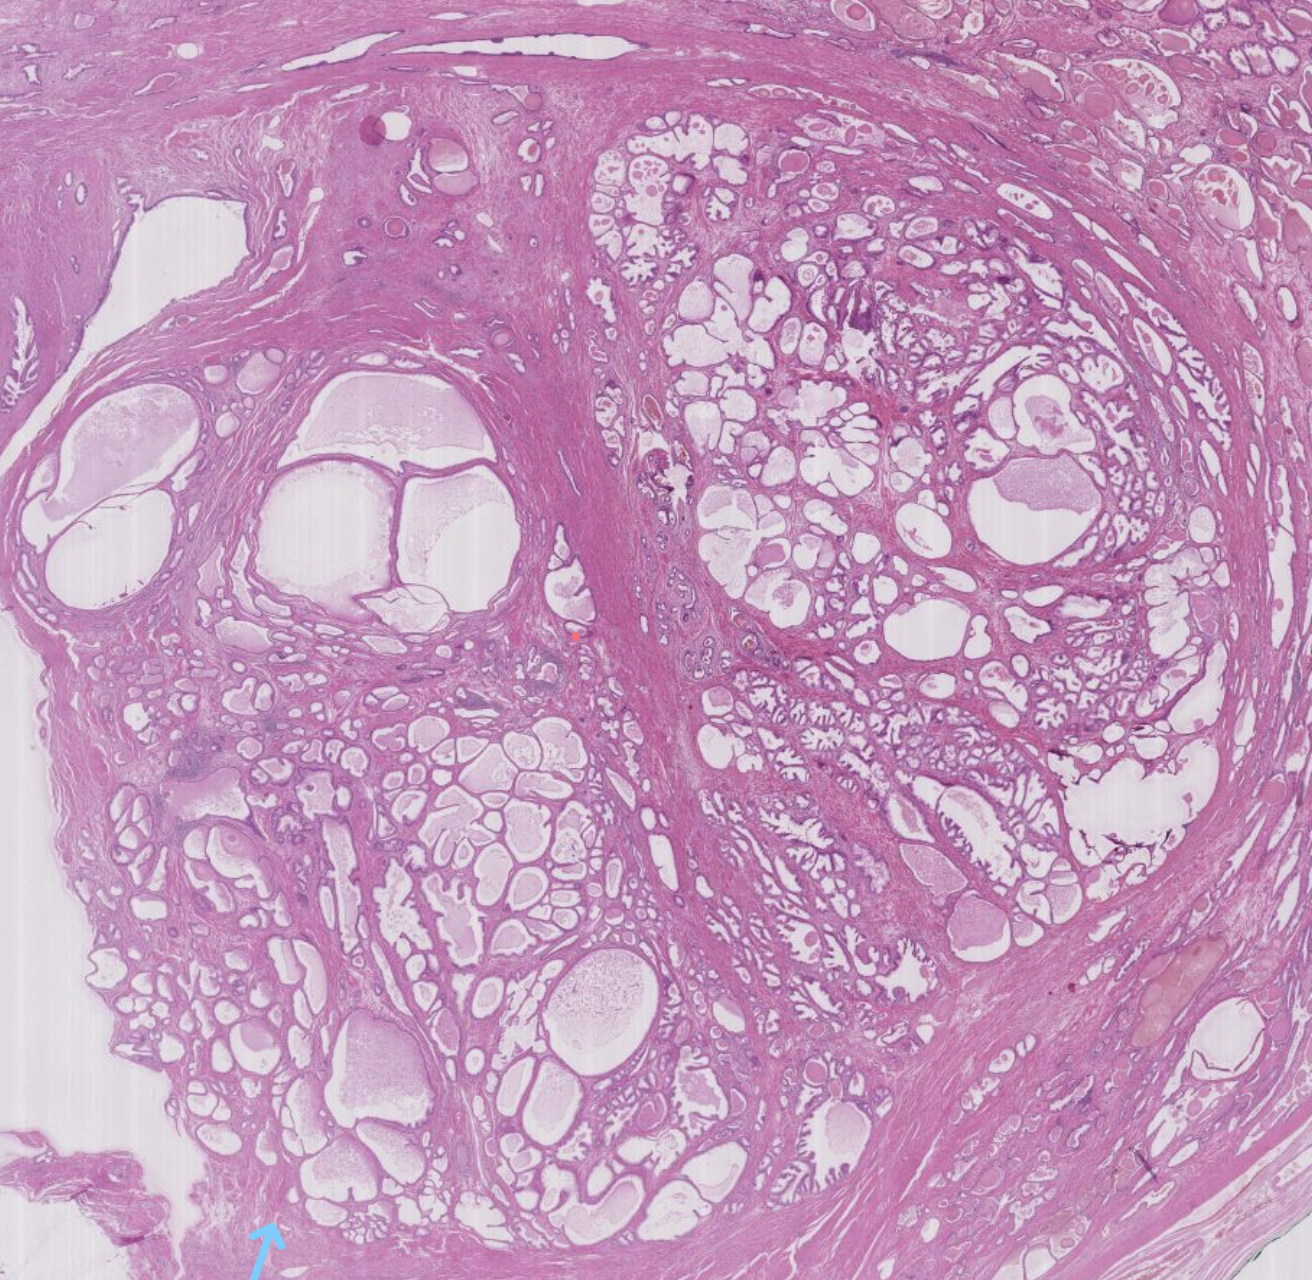

15) Was ist eine Knotenstruma? (Hyperplasie)

• Definition: Knotige Schilddrüsenhyperplasie

• Ursache: Verstärkte trophe Signale in der Schilddrüse

• Ergebnis: Vergrößerung (Hyperplasie ± Hypertrophie) der Follikel und Ausbildung von knotigen Veränderungen

• Histologie: Unregelmäßig vergrößerte Follikel mit Fibrose und regressiven Veränderungen

18) Wie entsteht aus einer Struma diffusa eine Struma nodosa? (Hyperplasie)

• Ursache: Unterschiedliche TSH-Empfindlichkeit der Follikelepithelien bei Struma diffusa

• Regressive Veränderungen:

• Fibrose

• Pseudozysten

• Nekrose

• Blutungen

• Mechanismus: Missverhältnis zwischen Wachstum und Vaskularisation

• Ergebnis: Knotige Form (Struma nodosa)